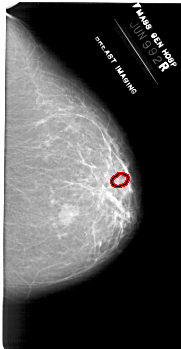

A_1953_1.RIGHT_MLO

RIGHT_MLO LINES 6871 PIXELS_PER_LINE 3631 BITS_PER_PIXEL 12 RESOLUTION 43.5 OVERLAY

FILE: A_1953_1.RIGHT_MLO.OVERLAY

TOTAL_ABNORMALITIES 1

ABNORMALITY 1

LESION_TYPE CALCIFICATION TYPE PLEOMORPHIC DISTRIBUTION CLUSTERED

ASSESSMENT 4

SUBTLETY 1

PATHOLOGY BENIGN

TOTAL_OUTLINES 1

BOUNDARY